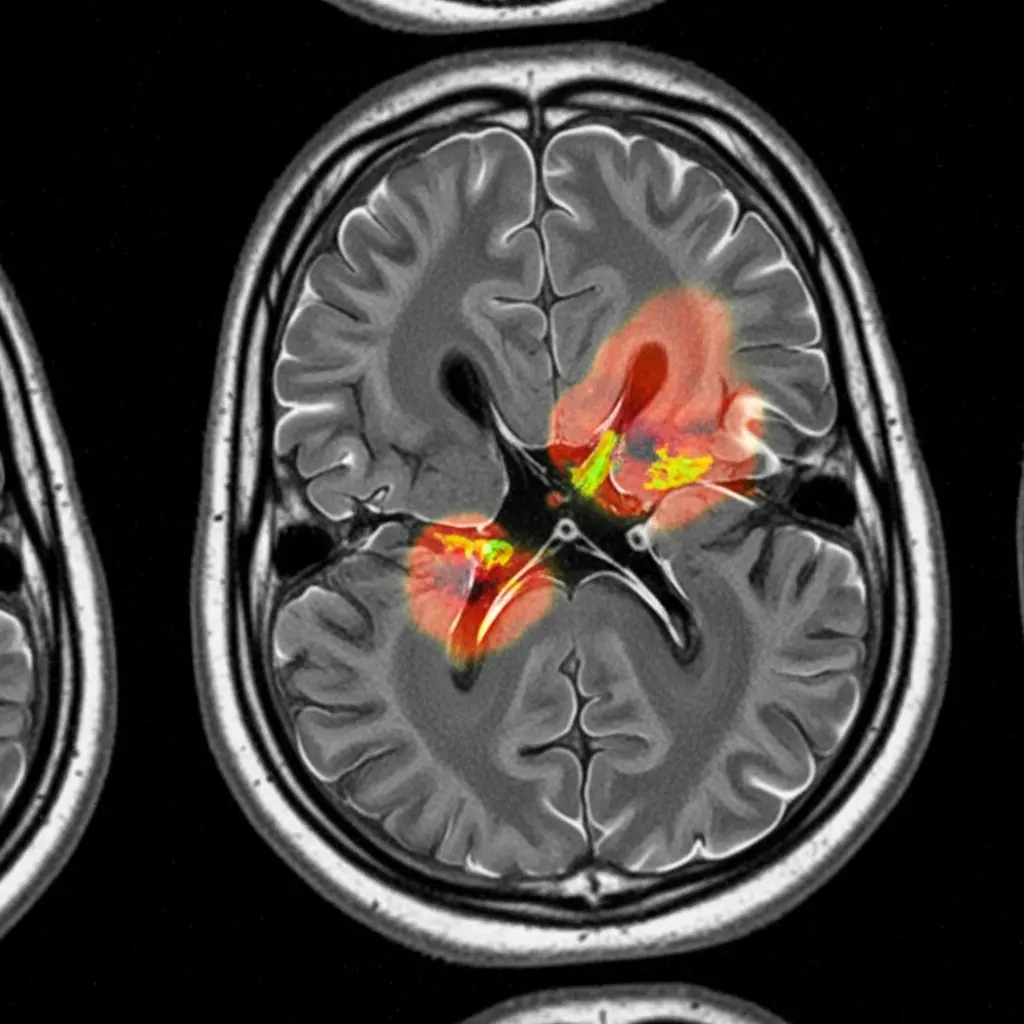

Scientists are tackling the crucial problem of effectively utilising foundation models for multi-modal medical imaging, a field currently hampered by difficulties in fusing information from diverse sources and adapting to complex tissue characteristics. Shadi Alijani, Fereshteh Aghaee Meibodi, and Homayoun Najjaran, all from the University of Victoria, present a novel framework addressing these challenges with sub-region-aware modality attention and adaptive prompting. This research is significant because it allows the model to intelligently combine imaging modalities specific to each area of a tumour, refining segmentation accuracy and demonstrably outperforming existing methods on the challenging BraTS 2020 dataset , particularly within the necrotic core. Their principled approach promises more accurate and robust foundation model solutions for medical image analysis, ultimately improving diagnostic capabilities.

This research introduces two key innovations, sub-region-aware modality attention and adaptive prompt engineering, to overcome these limitations and enhance segmentation accuracy. The attention mechanism allows the model to dynamically learn the optimal combination of imaging modalities for specific sub-regions within a tumor, while the adaptive prompting strategy leverages the inherent capabilities of foundation models like MedSAM to refine segmentation results.

Experiments conducted using the BraTS 2020 brain tumor segmentation dataset reveal that this approach significantly outperforms baseline methods, particularly in the notoriously difficult task of delineating the necrotic core sub-region. The team achieved this breakthrough by focusing on a principled and effective method for multi-modal fusion and prompting, paving the way for more accurate and robust foundation model-based solutions in medical imaging. This work establishes a new state-of-the-art performance in MedSAM-based brain tumor segmentation, offering a substantial improvement over existing techniques. The sub-region-aware modality attention mechanism enables the model to focus on the most informative data for each tumor component, necrotic core, edema, and enhancing tumor, improving the precision of segmentation.

Furthermore, the adaptive prompt engineering utilizes sub-region-specific prompts to guide the model’s attention, resulting in enhanced delineation accuracy and a more refined understanding of tumor boundaries. Through extensive experimentation, researchers provide a comprehensive analysis of the impact of these components, offering valuable insights into the effective design of multi-modal fusion and prompting strategies for foundation models in medical imaging. This research makes several key contributions to the field, introducing a novel framework and demonstrating its effectiveness on the challenging BraTS 2020 dataset. The study unveils a new approach to adapting foundation models, moving beyond traditional supervised learning methods that require extensive annotated data and struggle with generalization. By leveraging the inherent promptability of MedSAM and incorporating sub-region-specific information, the team has created a system capable of achieving superior segmentation performance and providing a more detailed analysis of brain tumor characteristics, ultimately advancing the potential for improved clinical diagnosis and treatment planning.

Scientists developed a novel framework to adapt foundation models for multi-modal medical imaging, addressing the challenge of effectively fusing information from diverse sources and accommodating heterogeneous pathological tissues. The research team engineered sub-region-aware modality attention and adaptive prompt engineering as key technical innovations within this framework, enabling dynamic focus on the most informative data for specific tumor regions. This approach allows the model to learn the optimal combination of modalities, such as MRI and CT scans, for each sub-region of the tumor, including the necrotic core, edema, and enhancing tumor, significantly improving delineation accuracy. Experiments employed the BraTS 2020 brain tumor segmentation dataset to validate the framework’s performance, utilising a dataset comprised of multi-modal brain scans.

The team implemented the sub-region-aware modality attention mechanism by dividing each tumor into distinct sub-regions and training the model to assign varying weights to each modality based on its relevance to that specific region. Adaptive prompt engineering was achieved by leveraging the promptability of the MedSAM foundation model, crafting sub-region-specific prompts to guide the model’s attention and refine segmentation boundaries. This technique harnesses the inherent capabilities of MedSAM, tailoring its performance to the nuances of each tumor sub-region. The study pioneered a method for dynamically adjusting the model’s focus, allowing it to prioritise information from different modalities depending on the characteristics of each tumor sub-region.

Scientists have developed a novel framework for adapting foundation models to multi-modal medical imaging, addressing the critical challenge of effectively fusing information from diverse sources and accommodating the variability of pathological tissues. Experiments utilising the BraTS 2020 brain tumor segmentation dataset demonstrate significant performance gains, particularly in segmenting the challenging necrotic core sub-region. The team measured Dice scores and Intersection over Union (IoU) to quantify segmentation accuracy, employing a 5-fold cross-validation strategy to ensure robust evaluation and reporting mean and standard deviation across folds. Statistical significance was assessed using a two-sided Wilcoxon signed-rank test, with p Initial experiments revealed that FLAIR achieved the highest single-modality Dice score of 0.8547 ±0.091, consistent with its clinical utility in highlighting pathological tissue.

The developed method attained a whole tumor Dice score of 0.900, competitive with the state-of-the-art nnU-Net (0.890). More impressively, the method demonstrated superior performance on enhancing tumor segmentation, achieving a Dice score of 0.900 compared to 0.820 for nnU-Net, representing a 9.8% improvement. The full framework, combining attention and prompting, achieved a Dice score of 0.9012 ±0.051, a significant improvement over the baseline fine-tuned multi-modal model. Detailed sub-region performance analysis revealed critical disparities, motivating the proposed framework. The enhancing tumor was segmented with high accuracy across modalities, while the necrotic core presented a significant challenge, with single modalities achieving Dice scores as low as 0.61. Multi-modal fusion provided the largest improvement for the necrotic core, increasing the Dice score to 0.64 ±0.14, but performance remained substantially lower than other sub-regions, highlighting the need for specialized approaches. Measurements.